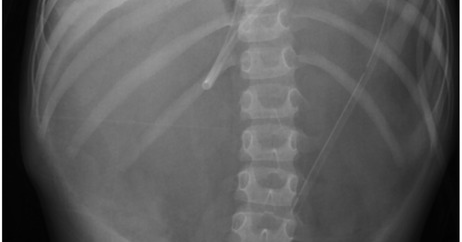

New Research: Necrotizing enterocolitis in a neonate with severe congenital pulmonary valve stenosis complicated by a postoperative right atrial thrombus: a case report https://t.co/TllkGASxLp

frontiersin.org

Congenital heart disease may increase the incidence of necrotizing enterocolitis, especially in low-birth-weight infants. We report a case of a newborn with ...